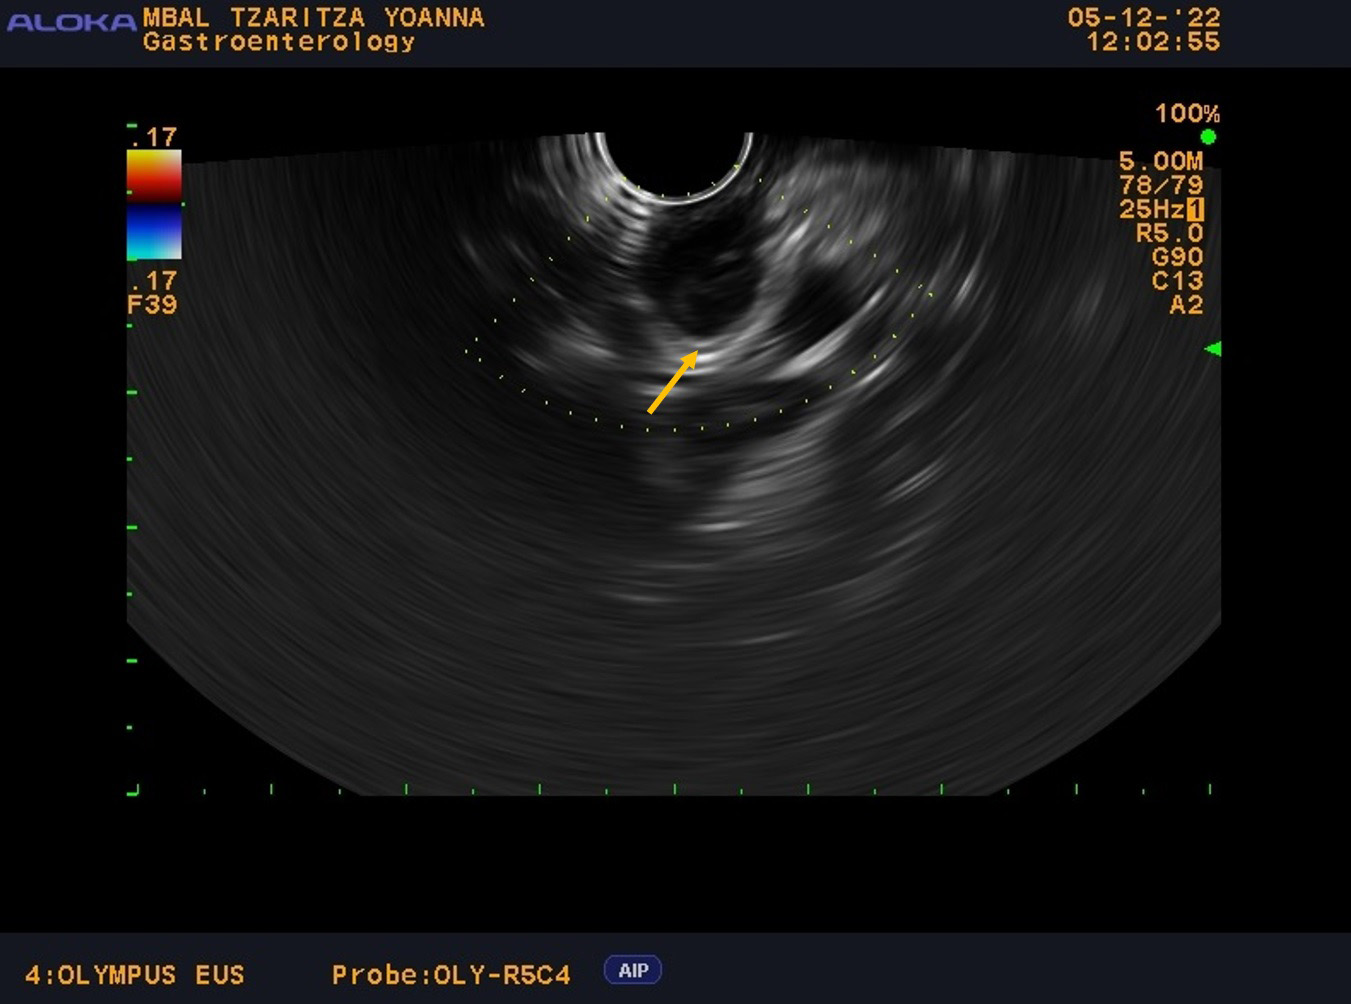

Throughout her hospital stay in our clinic, the patient exhibited normal laboratory results and no symptoms, without any other concomitant diseases or significant family history. From the physical examination (PE) the patient was slightly overweight with a body mass index (BMI)—29 without other pathological findings. The patient was scheduled for an EUS examination, which is the preferred modality for evaluating subepithelial lesions of the upper GI tract. During the EUS examination, an anechoic subepithelial lesion of the stomach was noted just below the oesophagogastric junction, corroborating the findings from the OGD. The lesion was 13.5 mm in size and displayed a typical “gut signature sign”, which is highly suggestive of a duplication cyst (Fig. 1). Given that other subepithelial lesions can appear intensely hypoechoic as lymphoma, leiomyomas, gastrointestinal stromal tumors (GIST), etc. and can mimic anechoic lesions, a CE-EUS was performed revealing enhancement confined to the wall of the lesion (Fig. 2) and confirming the diagnosis of a duplication cyst.

Fig. 1.

EUS examination with anechoic subepithelial lesion 13.5 mm in size at OGD and typical “gut signature sign”. Endoscopic ultrasound with the linear probe with anechoic subepithelial lesion 13.5 mm in size originating from the submucosal layer of the wall with “gut signature sign” highly suspicious for duplication cyst (the arrow). EUS, endoscopic ultrasound; OGD, oesophagogastroduodenoscopy.